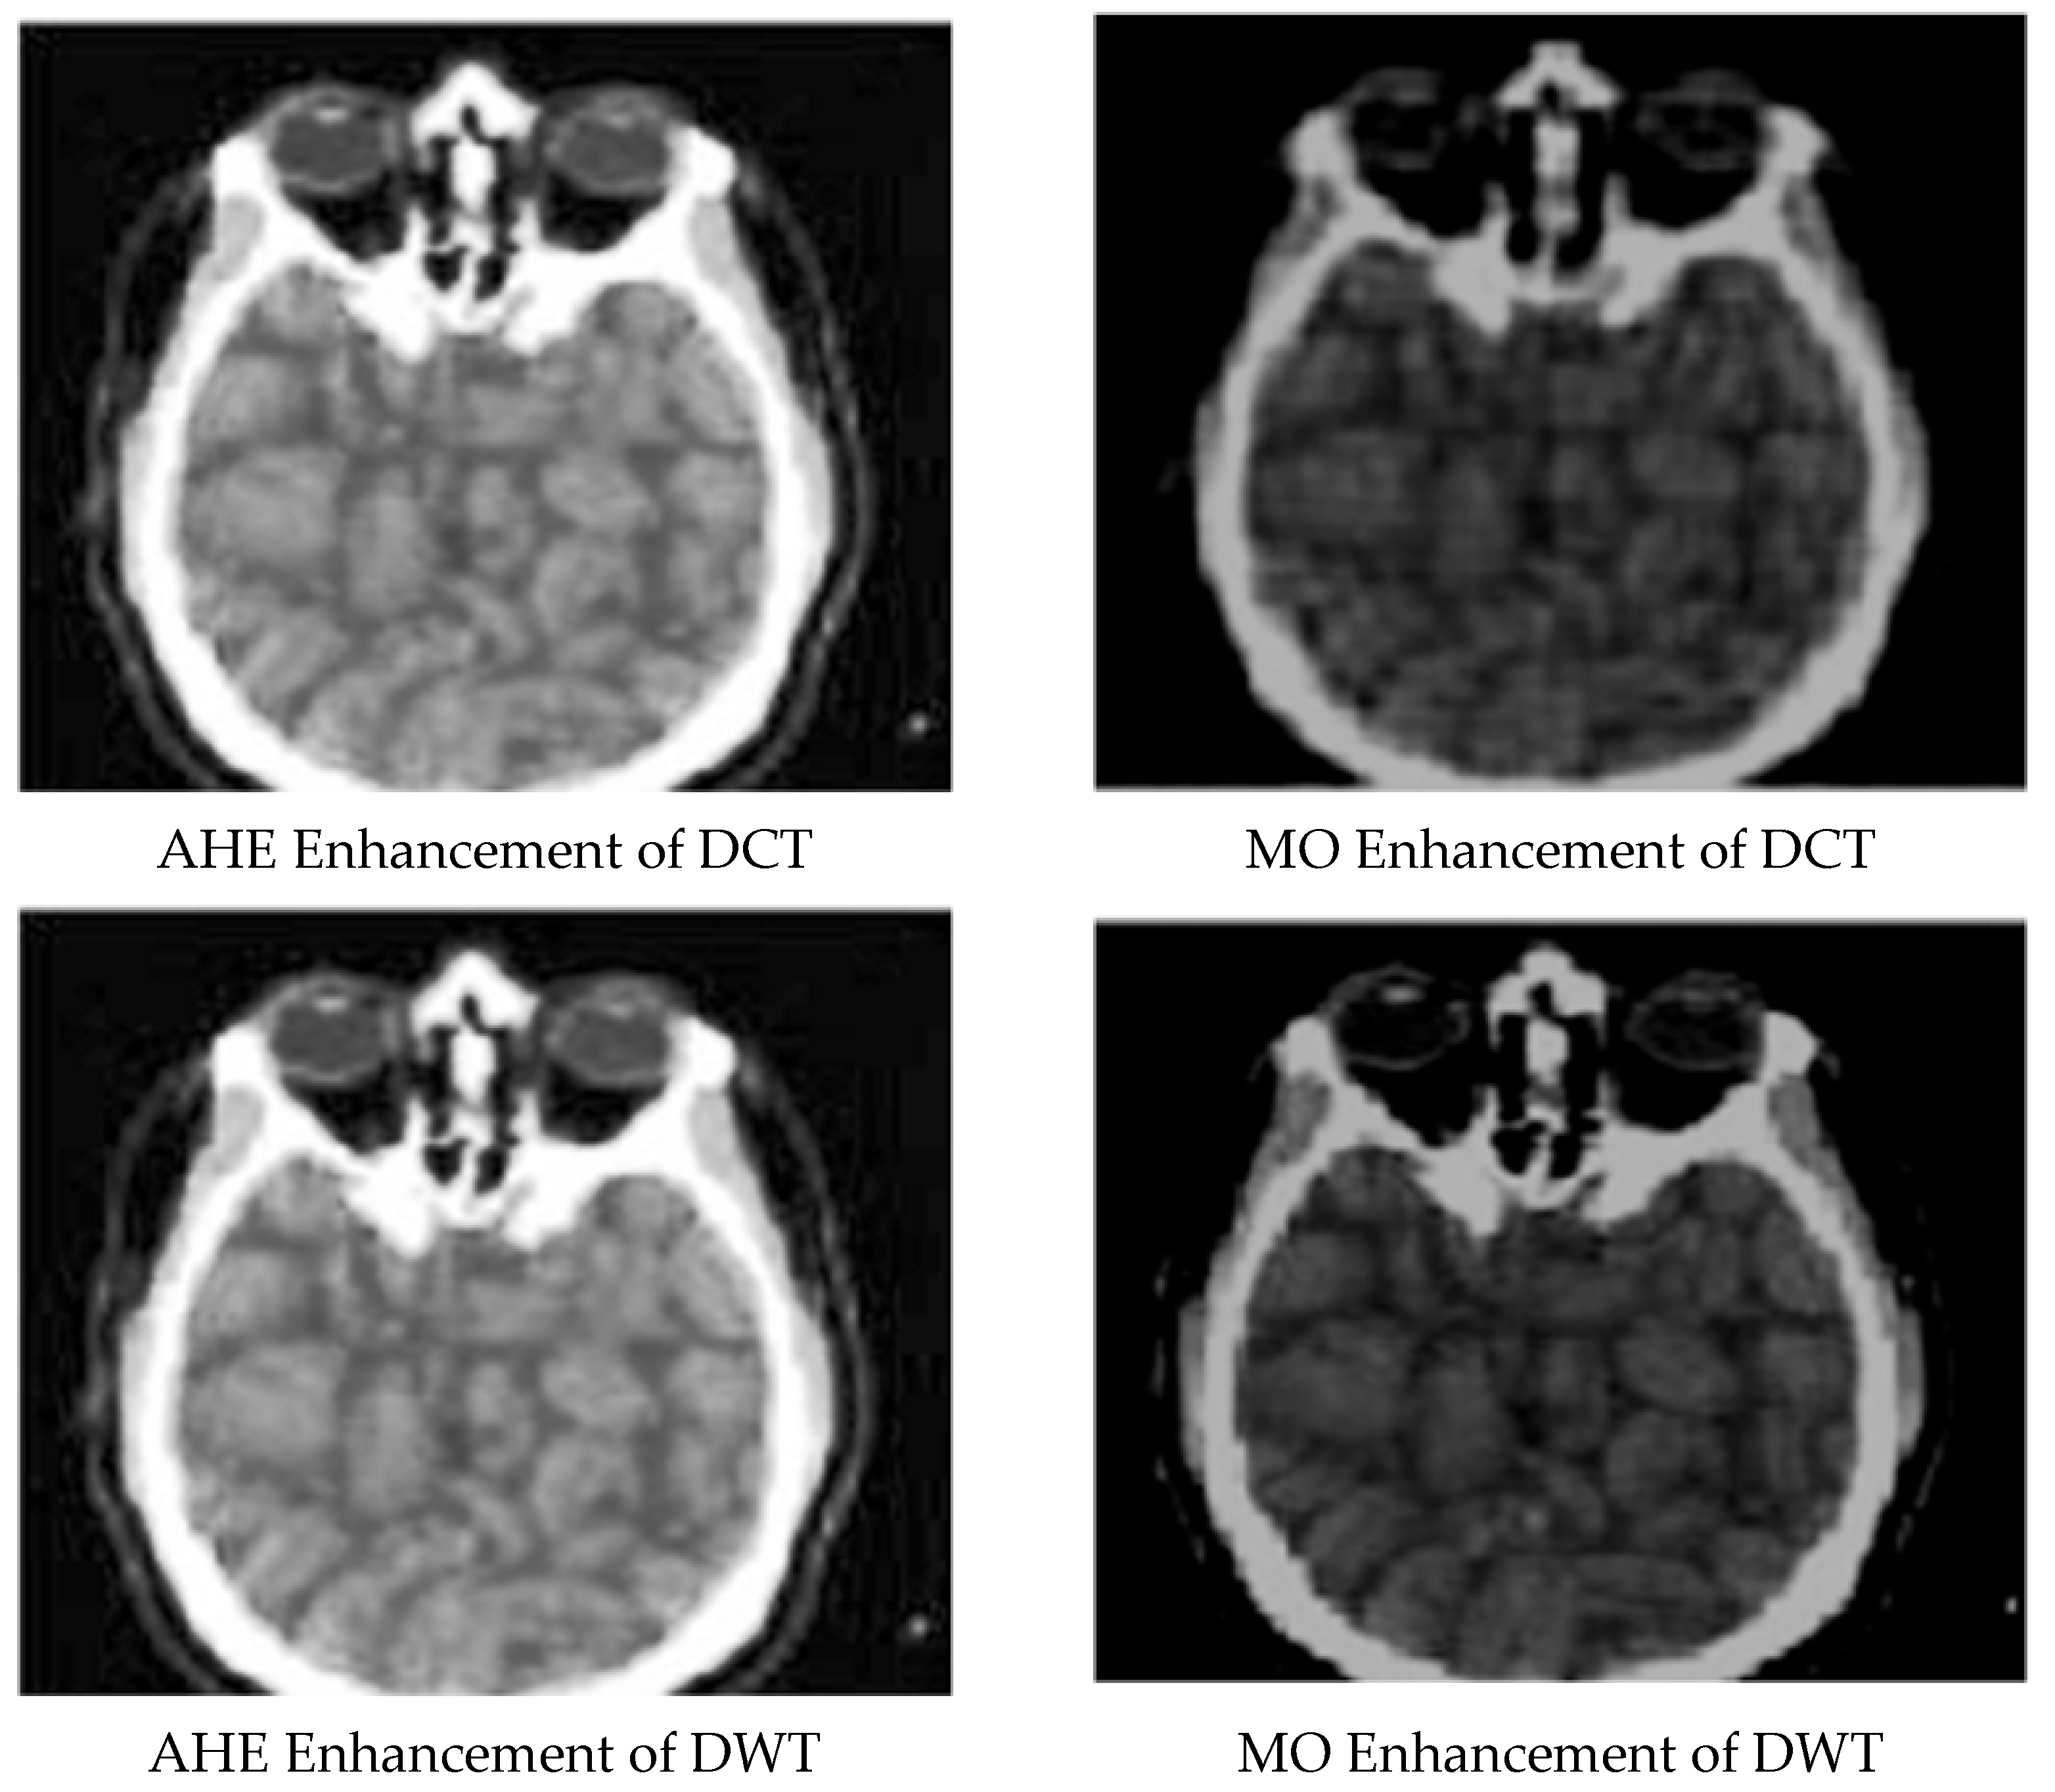

Enhanced and Compressed Output

5. Discussion

| 2 | AHE enhancement for DCT compressed image | 0.953323544 | 0.01256723 | 82.67223261 |

| 3 | DWT compressed image | 0.060732271 | 0.555070285 | 54.76541543 |

| 4 | AHE enhancement for DWT compressed image | 0.996540627 | 4.14 × 10−5 | 86.98046733 |

| 5 | MO enhancement for DWT compressed image | 0.919275875 | 0.012887986 | 72.76504215 |